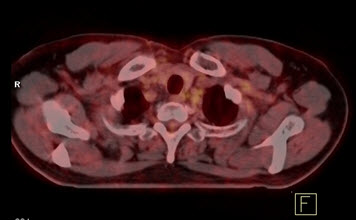

Hình 5. Bệnh nhân Nguyễn X.T., nam, 58 tuổi. Chẩn đoán: U lympho ác tính không Hodgkin, giải phẫu bệnh: WF6. Hình PET cho thấy tổn thương ở phổi, hạch, xương, tuyến thượng thận hai bên (mũi tên). Hình CT và PET/CT cho thấy tổn thương tăng hấp thu FDG tại vị trí tuyến thượng thận hai bên (mũi tên), max SUV=11,34.